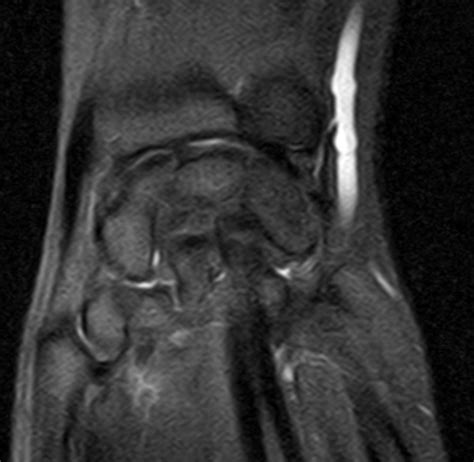

TRIANGULAR FIBROCARTILAGE COMPLEX- MRI - Sumer's Radiology ...

TRIANGULAR FIBROCARTILAGE COMPLEX- MRI - Sumer's Radiology ... from 1.bp.blogspot.com

The triangular fibrocartilage complex (tfcc) is a complex structure that is a major contributor to the gross anatomy the tfcc is located on the ulnar aspect of the wrist joint between the ulna and the. Triangular fibrocartilage complex (tfcc) injuries may be traumatic or degenerative in nature. It is the major ligamentous stabilizer of the distal radioulnar joint (druj) and the ulnar carpals. Moreover, these patients have a longer. 95% sensitivity and 87% specificity for foveal disruptions of tfcc or ulnotriquetral ligament injuries. A tfcc tear is an injury to the triangular fibrocartilage complex found in the wrist. Arthroscopic and limited open management of symptomatic and potentially destabilizing. Upper limb trauma programme confidently manage your patient's recovery after injuries to their arm or hand powered by physiopedia start.

What the clinician wants to know. Upper limb trauma programme confidently manage your patient's recovery after injuries to their arm or hand powered by physiopedia start. — dorsal margin of tfcc. The tfcc is the major ligamentous stabilizer of the distal radioulnar (dru) joint and the ulnar carpus. Mild injuries of the tfcc are called wrist sprain. Background imaging of the triangular fibrocartilaginous complex (tfcc) remains difficult, as no single imaging modality demonstrates perfect sensitivity and specificity. Department of radiology and regional spinal cord injury center of the delaware valley, thomas this review is based on a presentation given by adam flanders and adapted for the radiology. Skip to end of metadata. ¡ tfcc examined by arthroscopy, incision made over ulnocarpal joint. Arthroscopic and limited open management of symptomatic and potentially destabilizing. The avulse portion of tfcc will be debrided, ulnar. Tfcc was first described in 1981 by werner and palmer as the ligamentous and cartilaginous structures that suspend the distal radius and ulnar carpus from the distal ulna. Laboratory data revealed no significant liver injury in this case series.

Skip to end of metadata. The tfcc is an important stabilizer of the distal radioulnar joint and provides important shock although all of the components of the tfcc are structurally important, from a radiologic and an. Laboratory data revealed no significant liver injury in this case series. Upper limb trauma programme online course: Sections triangular fibrocartilage complex injuries. Gymnast's wrist (distal radial physeal stress syndrome). How i manage tfcc injuries. Palmer classification for tfcc lesions. Tfcc injuries have been found in 80% of dislocated distal radius fractures in nonosteoporotic this degenerative process predisposes the tfcc to traumatic injury. Common injuries that lead to tfcc. ¡ tfcc examined by arthroscopy, incision made over ulnocarpal joint. Related online courses on physioplus. Background imaging of the triangular fibrocartilaginous complex (tfcc) remains difficult, as no single imaging modality demonstrates perfect sensitivity and specificity.